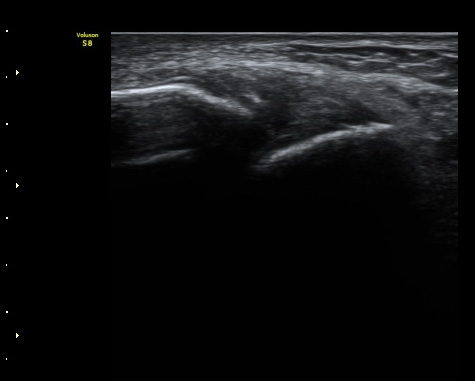

ÃÊÀ½ÆÄ°¨½ÃÇÏ °Å°ñºñ°ñÀÎ´ë °ßÀΰ˻翡¼­ °ñÆíÀÇ ¹ú¾îÁüÀÌ °üÂûµÊ(µ¿¿µ»ó 1).

3ÁÖ ÈÄ ÃßÀû°Ë»ç¿¡¼­ ¹Ú¸®µÈ°ñÆíÀÌ °üÂûµÇ°í ÀδëÀÇ Àú¿¡ÄÚ ºÎÁ¾Àº ¾à°£

Áõ°¡µÈ ¼Ò°ßÀ» º¸ÀÓ(±×¸² 3, 4).